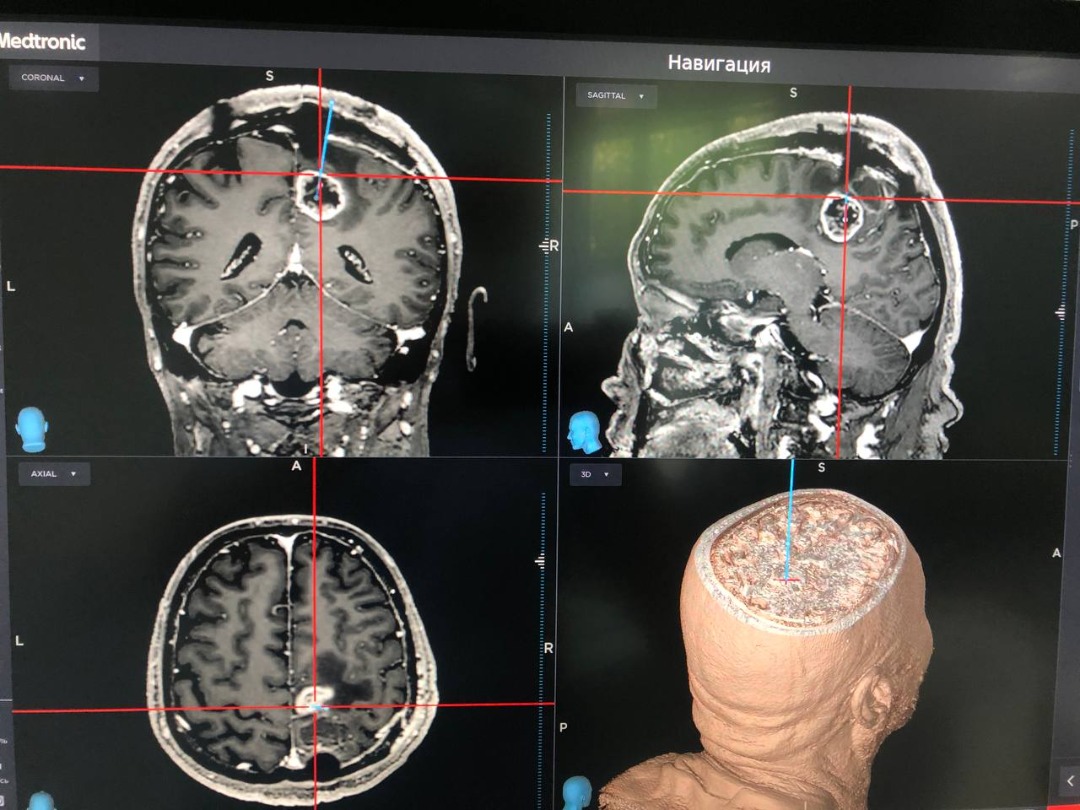

По его данным, это медоборудование помогает оперативно и с максимальной точностью определять место расположения новообразований в головном мозге и использовать наикратчайший рациональный хирургический доступ. Оно позволяет значительно уменьшить площадь трепанации черепа и риски повреждения близлежащих важных структур головного мозга.

«С появлением нейронавигационной системы в нашем Нацгоспитале значительно сократились послеоперационные осложнения. Нейронавигационный аппарат позволяет в реальном времени определить локализацию и близлежащие важные структуры головного мозга. Это минимизирует риск повреждения критически важных участков головного мозга», — подчеркнул заведующий отделением нейрохирургии Национального госпиталя, профессор, доктор медицинских наук Буранбек Дюшеев.